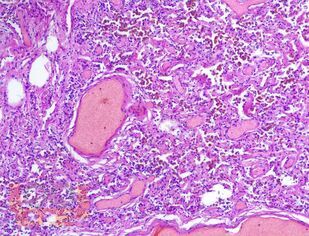

В пособии представлены цветные иллюстрации микропрепаратов и соответствующее им морфологическое описание. Детально освещены основные, наиболее важные гистологические изменения внутренних органов, позволяющие на светооптическом уровне диагностировать и дифференцировать между собой разнообразные патологические состояния. Представлены микрофотографии с гистохимическими окрасками различных тканей, использование которых помогает верифицировать специфические патологические процессы.